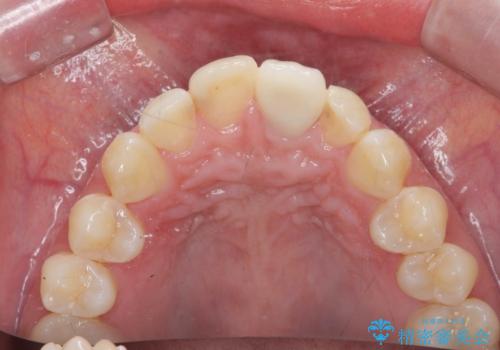

前歯の変色を改善するセラミッククラウン治療

- 以前に前歯を強打し、変色してきた前歯の審美性の改善を希望されて来院されました。

X線検査の結果、変色をきたしている歯は根尖病変が存在し、神経が失活している状態でした。

根管治療を行ったのち、セラミッククラウンで審美性を改善していきます。

歯科技工士との綿密な打ち合わせで、非常に自然なセラミッククラウンを作製することができました。